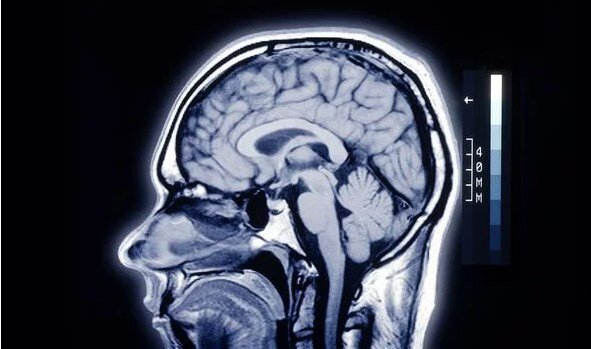

ОСП часто связаны с остановкой сердца, тяжелыми черепно-мозговыми травмами или потерей сознания и характеризуются видениями света в конце туннеля, видениями умерших близких или внетелесными переживаниями.

Эту тему изучали исследователи Манчестерского столичного университета Нил Дагналл и Кен Дринкуотер. В статье для The Conversation они обсудили наиболее вероятные триггеры околосмертных переживаний, такие как нейрохимические реакции в мозгу в момент травмы.

Ученые предложили два типа околосмертных переживаний, которые производятся разными полушариями мозга:

1. ОСП, возникающие в результате активности левой половины мозга, могут привести к изменению чувства времени или ощущению полета.

2. Околосмертные переживания, возникающие в правой половине мозга, могут привести к видениям мертвых людей или к голосам.

Височные доли мозга также могут играть роль в околосмертных переживаниях, поскольку эта часть мозга участвует в обработке воспоминаний и сенсорной информации.

Некоторые эксперты предположили, что околосмертные переживания это галлюцинации, вызванные высвобождением диметилтриптамина (ДМТ) мозгом, когда человек находится на грани смерти.

ДМТ мощное психоактивное вещество, часто ассоциирующееся с духовными и мистическими переживаниями.

Ещё одна теория предполагает, что околосмертные переживания вызываются недостатком кислорода в мозге - так называемая церебральная аноксия.

Недостаток кислорода потенциально вызывает судороги в височной доле, которые вызывают галлюцинации.

Другая популярная теория утверждает, что околосмертные переживания вызываются умирающими клетками мозга.

Так называемая гипотеза умирающего мозга могла бы объяснить галлюцинации, вспоминаемые многими пациентами.